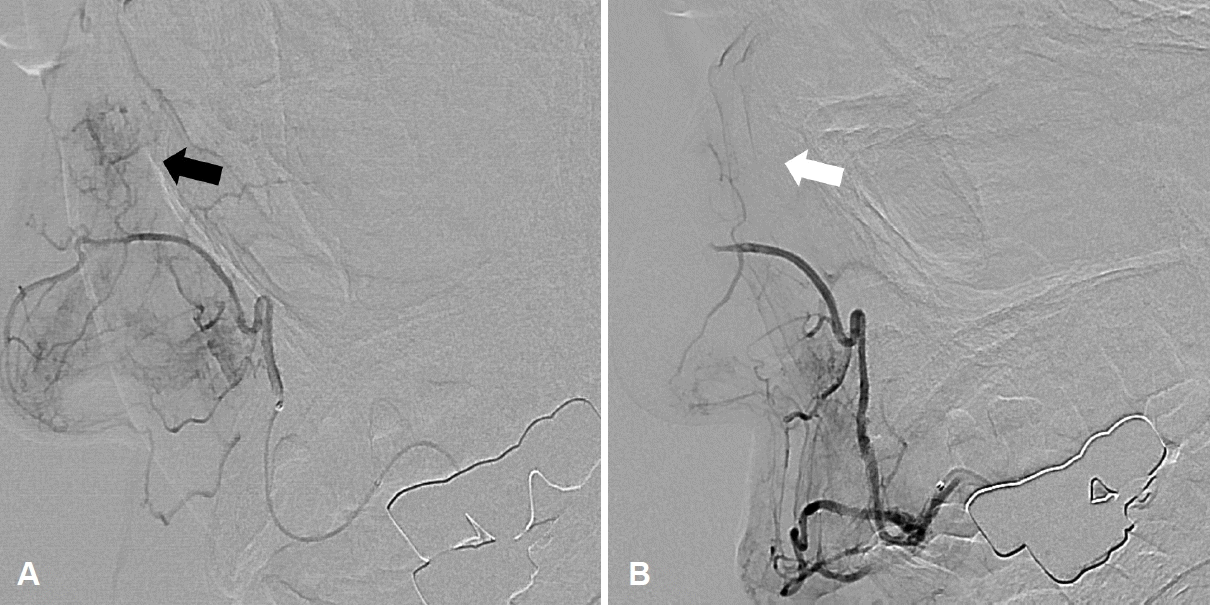

Preoperative biopsy was not indicated due to the risk of bleeding, and the patient underwent angiography with embolization before surgery because of the large-sized tumor and the expected risk of intraoperative bleeding. Angiography identified the vascular tumor originating from the lateral nasal branch of the right facial artery (Fig. 3). None of the patients was preoperatively diagnosed with angioleiomyoma, and transnasal endoscopic excision was performed in all patients. Histopathological examination confirmed the diagnosis of angioleiomyoma, and no significant intraoperative complications such as bleeding, were encountered in any case.

Preoperative angiography in patient 5. Blood supply from the lateral nasal branch of the right facial artery was noted (A, black arrow). After embolization, faint staining was still noted, but the blood flow was sluggish (B, white arrow).